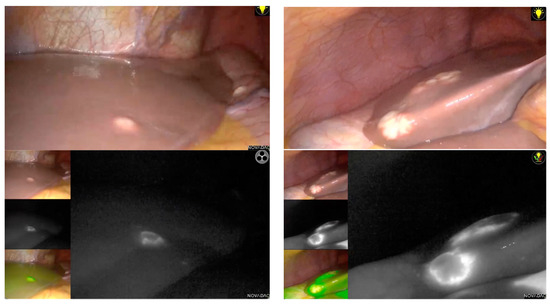

| Technique | Location of Tumors Detected | Tumor Margins | Detection of Missing Tumors from Preoperative CT Scan | Availability in OR | Disadvantages |

|---|---|---|---|---|---|

| Intraoperative ultrasound | Superficial or deep | Location relative to veins | Yes | Available | Technicality |

| Indocyanine green fluorescence | Only superficial | Real-time visualization | Yes, if superficial | Available | No deep lesion visualization |

| 3D models | Superficial and deep | Location relative to anatomical structures | No | Not available | Location of tumor detected only if by preoperative CT-scan |